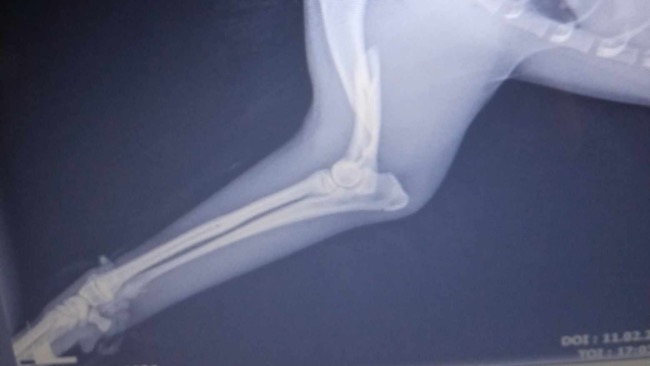

Kiedy pomoc nadeszła okazało się że maluszek ma złamaną lewą łapkę.

Po prześwietleniu w klinice okazało się że złamanie jest na tyle poważne iż będzie musiał przejść natychmiastową operacje aby mógł wrócić do sprawności.